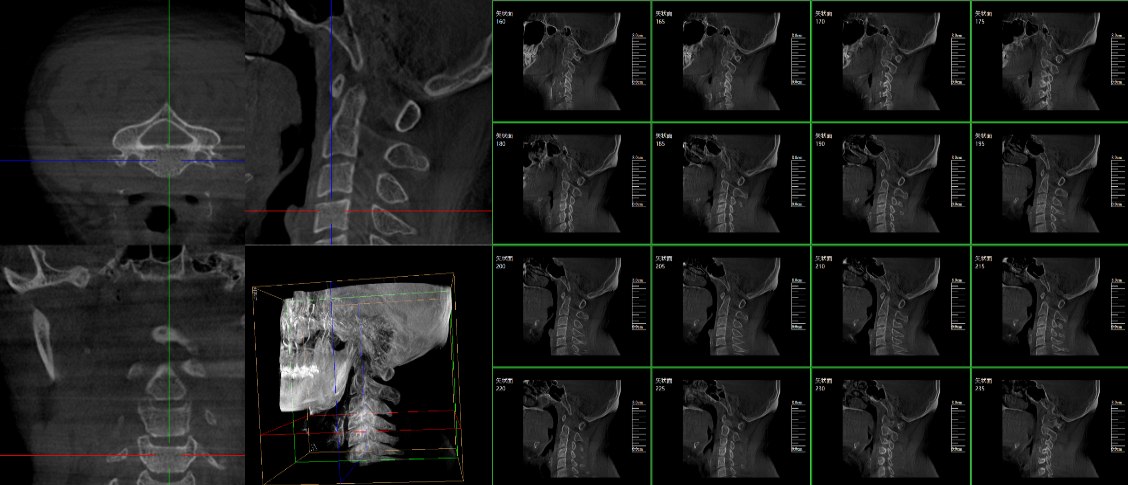

PLX7500三維c型臂脊柱外科臨床應用圖像

脊柱外科的應用:有研究表明,在三維c型臂圖像引導的下頸椎或胸椎后路螺釘置入術中,螺釘正確置入率可達92.7%,在三維c型臂圖像引導的椎間孔腰椎椎間盤融合術中,術者被輻射總量明顯降低。此外三維c型臂可以搭配骨科手術導航和機器人使用,能將該過程智能化和準確化,進一步提高螺釘的植入率。